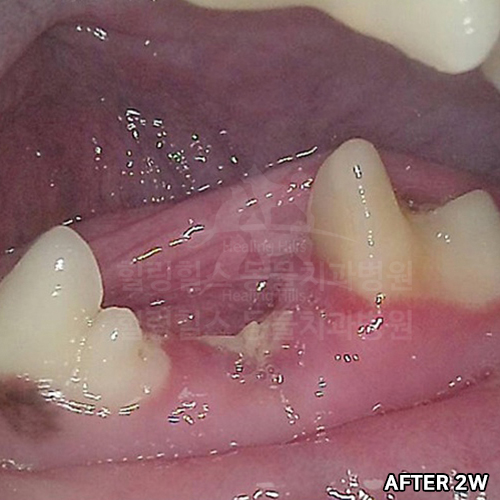

[강아지어금니파절, 치아흡수, 치수괴사, 치근단농양, 치근단공개방....! 편측절제(Hemisection)]

샘플